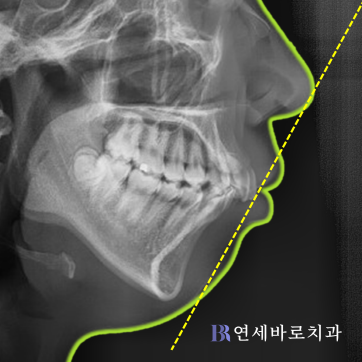

해당 환자분의 경우에는 상악만

2곳에 발치를 진행한 케이스로서,

아래턱이 작은 무턱이기 때문에

편악발치로 상악과 하악의 균형을

적절한 수준으로 맞춰주었습니다.

그러면서 윗니와 아랫니 간의

전후적인 불균형을 바로잡았으며,

덧니 때문에 심하게 겹쳐진 곳을

가지런하게 만들어드렸습니다.

외모적으로도 예전보다

좋은 변화가 나타났는데요.

입술 아래쪽 근육의

긴장감이 줄어들었습니다.

호두턱 느낌이 사라졌으며,

돌출입도 훌륭하게 해소되었습니다.